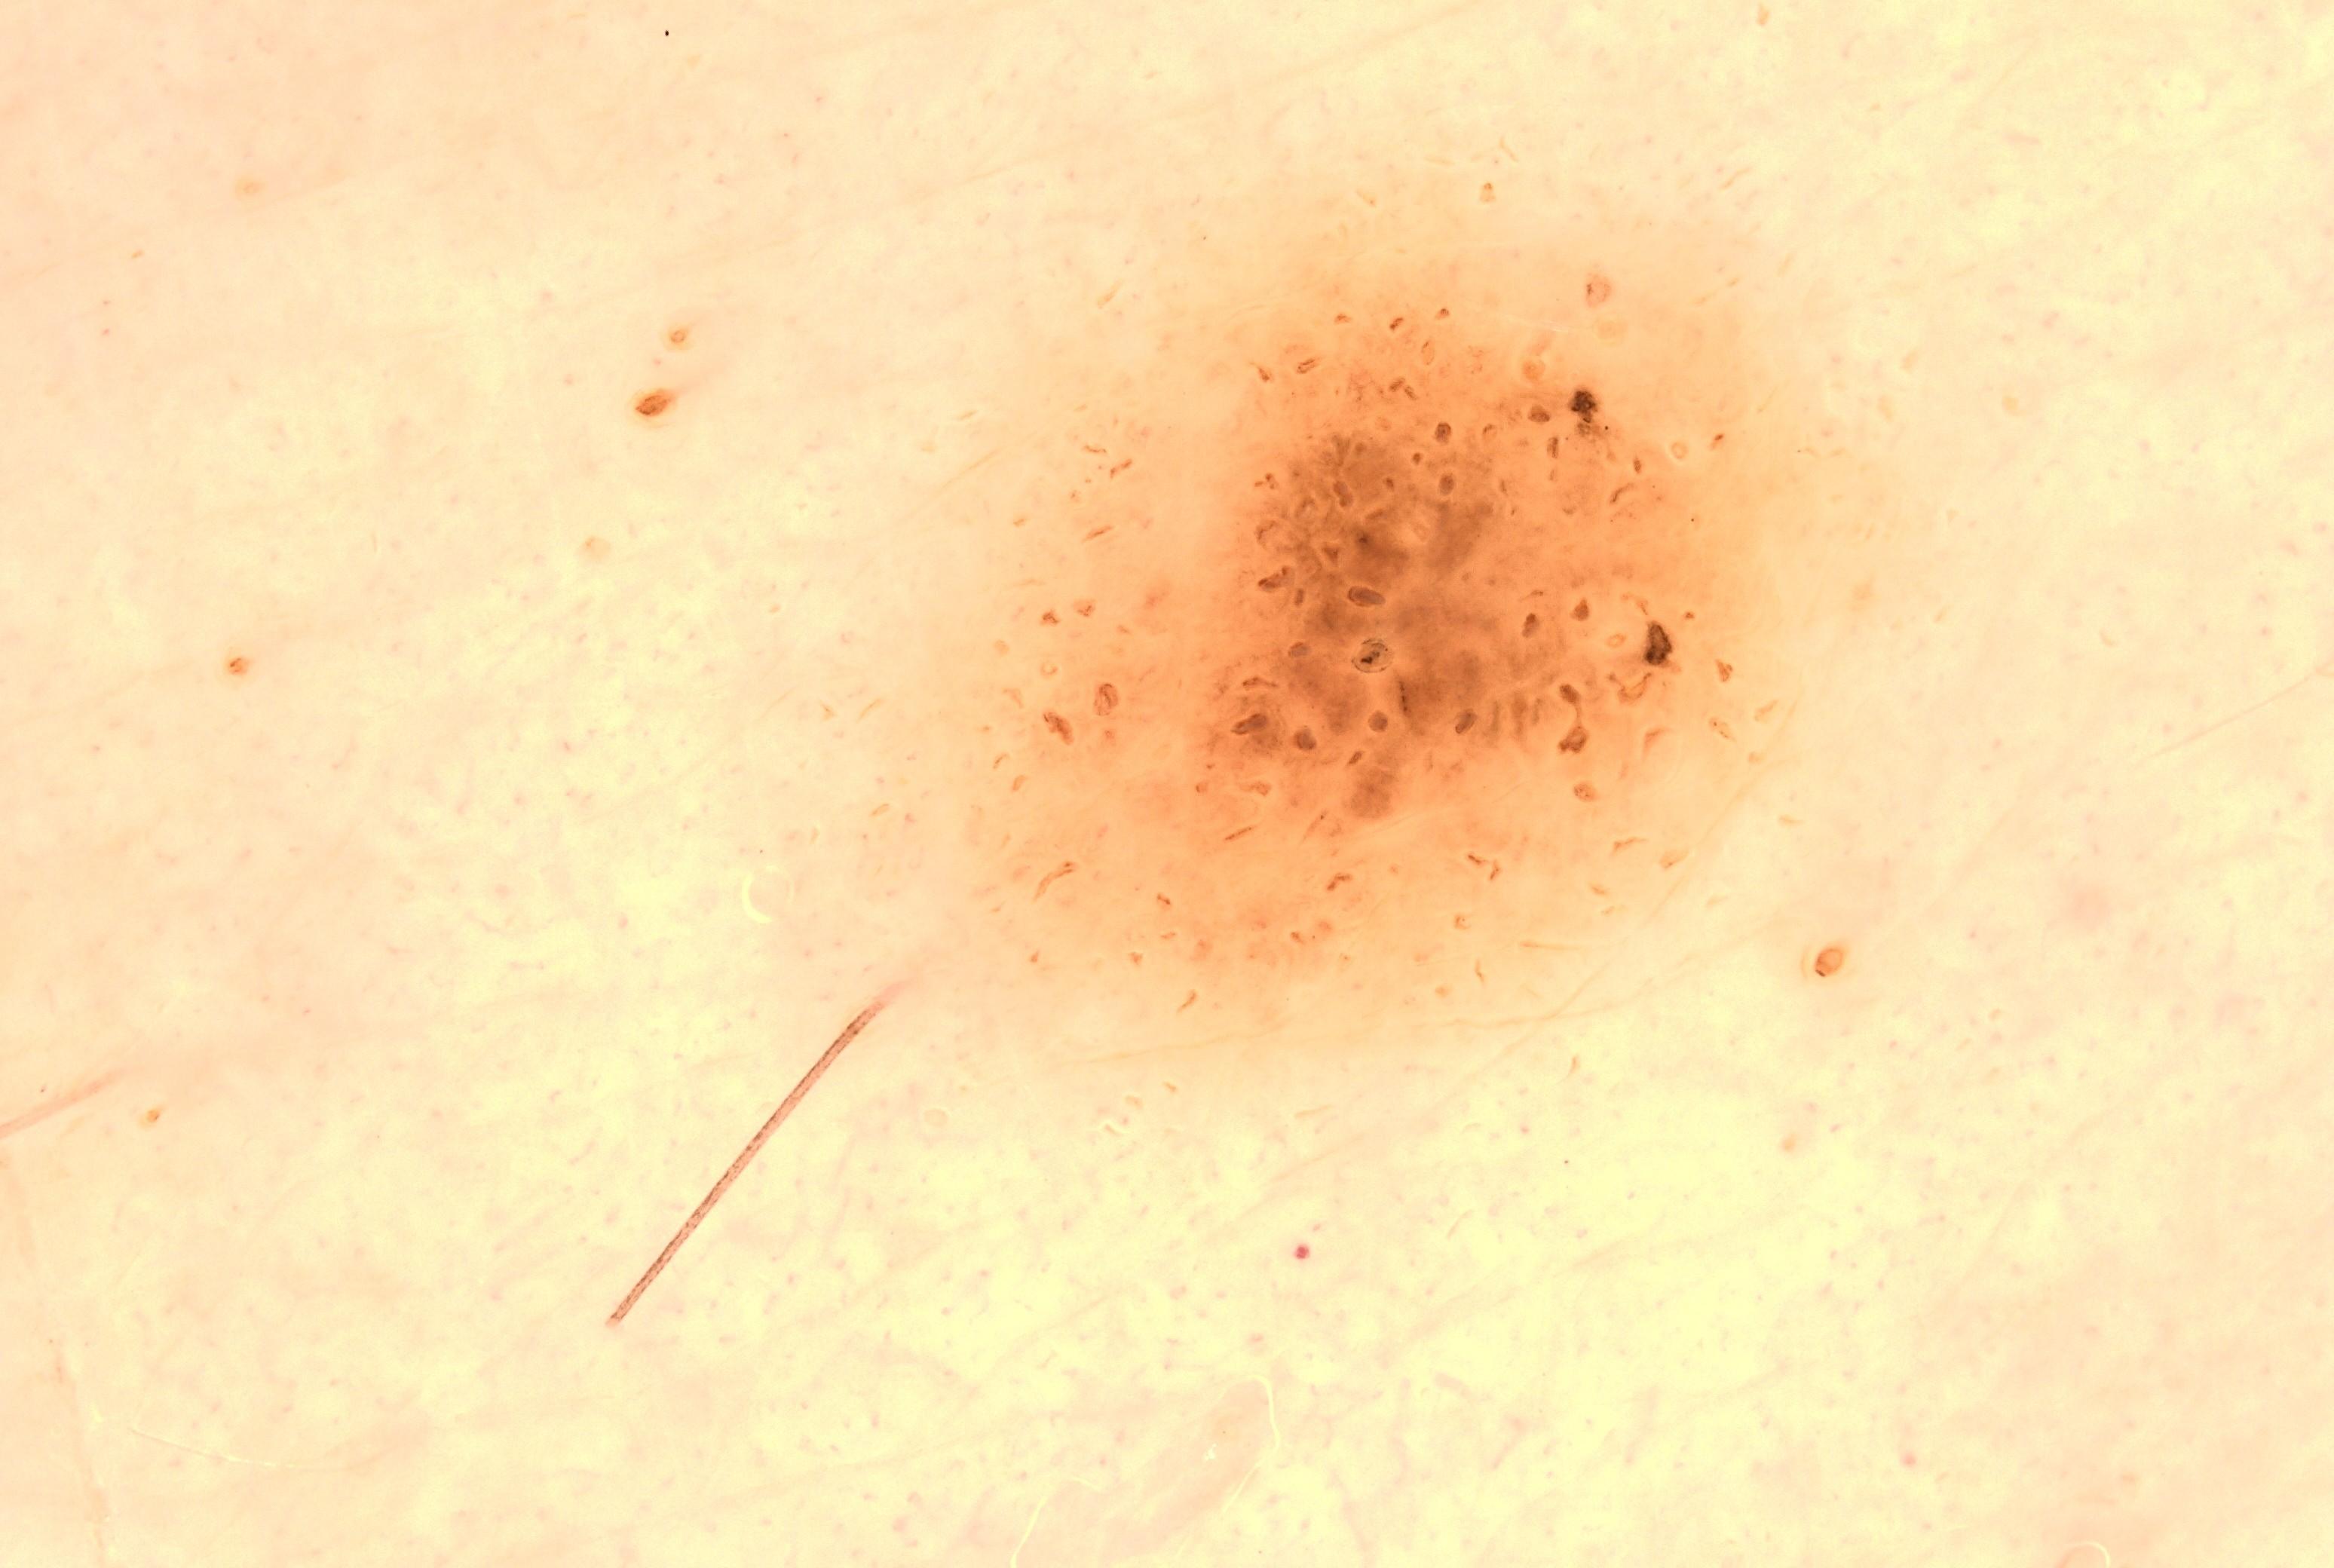

ISIC_8738639

acquisition_day 157

age_approx 25

anatom_site_1 Upper extremity

anatom_site_general upper extremity

diagnosis_1 Benign

family_hx_mm True

fitzpatrick_skin_type I

image_manipulation instrument only

image_type dermoscopic

lesion_id IL_0715197

patient_id IP_1618877

personal_hx_mm True

sex female